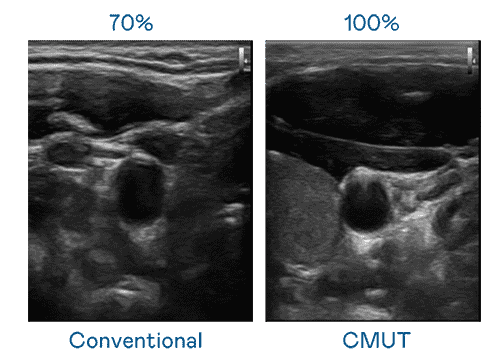

CMUT 技术是一种用电容式微机电元件来产生超音波讯号的技术。。。与传统 PZT 压电式技术相比,,CMUT 频宽增加 30%,,,,更宽频的超音波讯号让影像解析度大幅提升,,,,是实现高影像品质医疗超音波扫描、、、、促进精准医疗发展的关键技术。。。

大频宽带来超清晰影像

超音波影像的解析度高低,,,,首先取决于探头能发出的讯号频宽。。。28国际 CMUT 可提供高清晰的超音波讯号,,提供高频宽、、、、高灵敏度、、、、影像纹理细节更高的超音波影像,,,协助医护人员缩短影像判读时间及利用精准的医疗影像进行诊断。。。